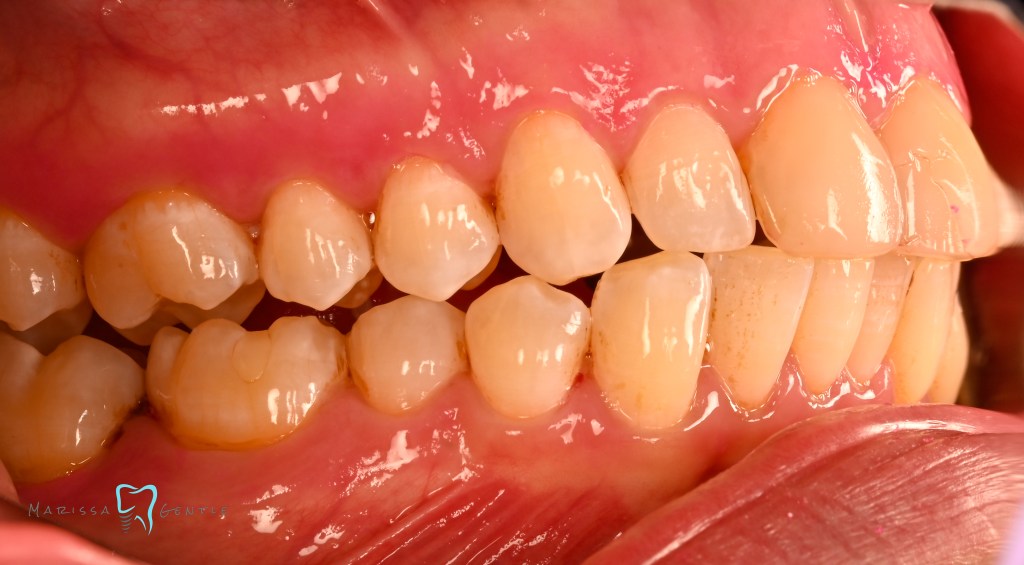

Patient presented with esthetic concern, composite veneers were placed 3 years prior. Patient’s chief complaint is twisted #7, thickness of the composite veneers and now chipping. The veneers were placed initially due to Enamel hypoplasia. Clinically relevant information: the patient wears a mandibular advancement device as treatment for sleep apnea, malocclusion noted edge to edge. Zirconia crowns planned #7-10

Current composite veneers are defective and caries are clinically present